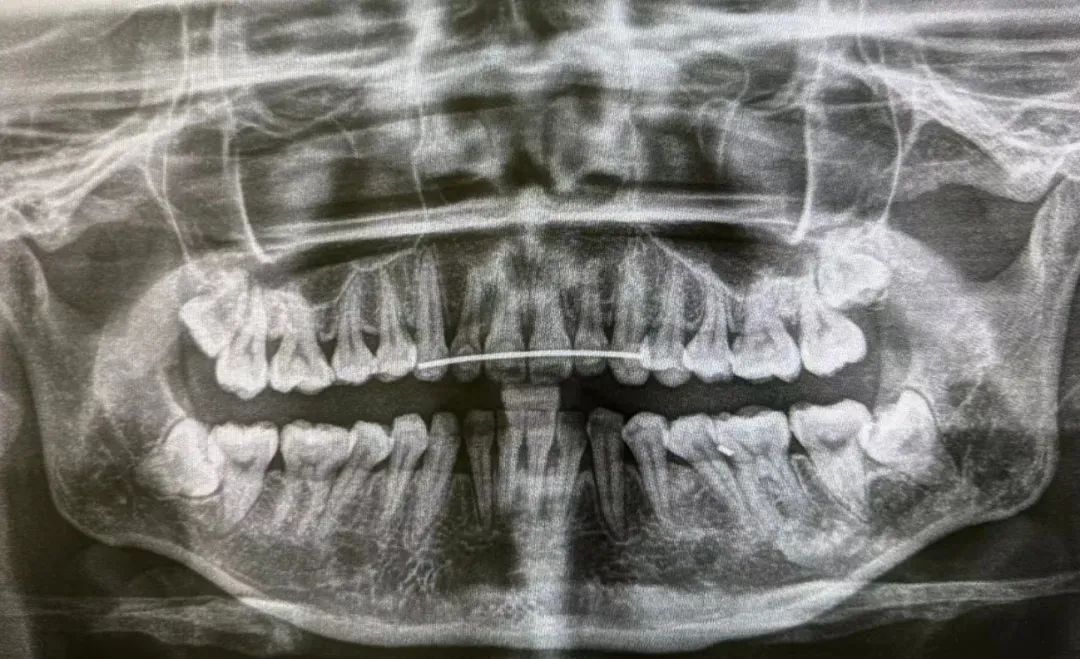

▲骑行者被摔后的牙齿情况

▲进行处理后的牙齿情况